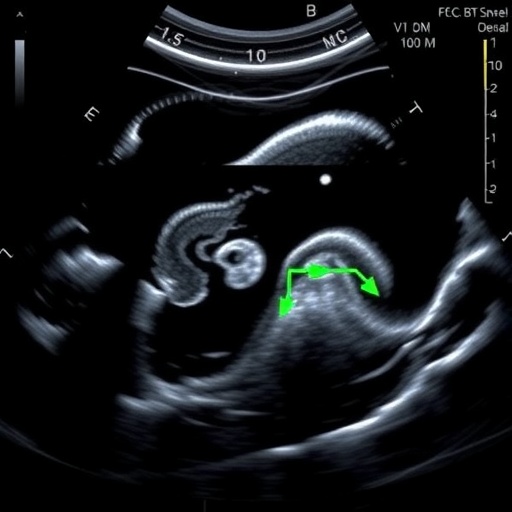

Utilization rates of bowel ultrasound further elucidate the divide between potential and practice. Where available, BUS is employed selectively rather than as a routine monitoring tool for at-risk neonates. This conservative approach appears tied to both entrenched reliance on abdominal radiographs and skepticism regarding the sensitivity and specificity of ultrasound findings in NEC. Nonetheless, emerging evidence underscores BUS’s superiority in detecting bowel wall thickening, pneumatosis intestinalis, and portal venous gas—hallmarks of NEC that are often subtle or delayed on X-rays.

Intriguingly, the technological sophistication of ultrasound equipment also plays a role in effective usage. Institutions with access to high-resolution probes and portable units report smoother incorporation of BUS into bedside assessments. Portable ultrasound devices are particularly advantageous in NICUs, allowing real-time imaging at the incubator without transferring critically ill infants, thereby reducing infection risk and transport-associated stress.

The clinical implications of enhancing BUS accessibility are profound. Early and accurate detection of NEC can dramatically alter patient trajectories, enabling prompt surgical consultations or targeted medical therapy. Furthermore, BUS can assist in monitoring disease progression, guiding nutritional management, and alerting clinicians to complications like bowel perforation or strictures, which demand immediate intervention.